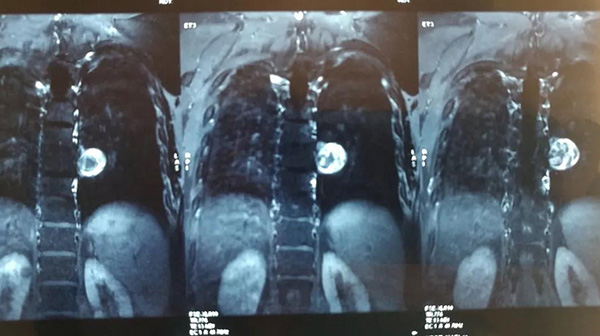

近期,家住齐齐哈尔市龙沙区的张先生因行走无力,来到附近医院就诊,其胸椎核磁共振提示,胸腔内长了一个巨大肿物且侵袭了胸椎管及胸腔,因手术难度大,技术要求高,术中稍有不慎将导致患者瘫痪、胸膜破裂或大血管损伤破裂,甚至死亡,多家医院便都拒绝了张先生的手术需求。因症状一直得不到缓解,辗转多家医院无果,张先生一度陷入了深深的痛苦之中。医生建议他去北京的大医院走走看看,如果前往北京治疗,除了面临高额的手术费用,还要考虑到疫情期间是否可以如期挂号、就诊,难度可想而知。一个偶然的机会,张先生得知齐齐哈尔市第一医院骨外二科主任罗先国在骨科疑难病例的诊治方面颇有建树,于是便在家人的陪同下找到罗先国。

认真阅片并详细查体后,罗先国告知张先生:不用担心,这个手术我们有信心,可以成功完成。面对患者对生命的渴求,罗先国带领团队进行了充分的术前准备,精心制定了手术方案。在相关科室的紧密配合下,为其顺利实施了手术,整个术程十分顺利,巨大肿物被完整切除,神经、胸膜、大血管均完好无缺。术后,患者便可自行下地行走,恢复速度令人称奇。